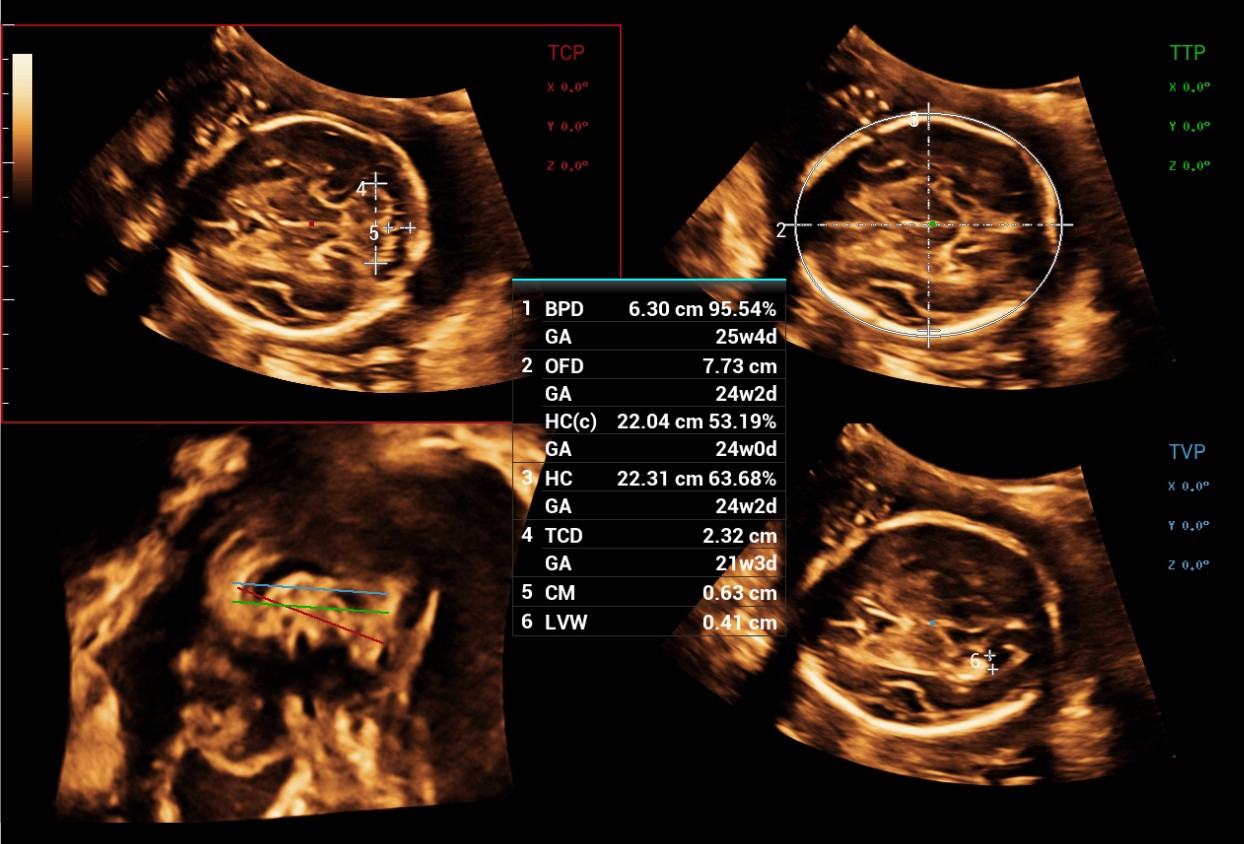

The Consona features new and concrete solutions, that efficiently help you to carry out smooth diagnoses for extensive type of patients. You will find highly powerful tools available on this series to keep you stay ahead in Obstetrics and Gynecology diagnosis.

Image Gallery